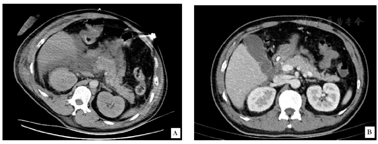

腹部增强CT示胰腺肿胀,增强扫描实质未见明显异常强化,胰腺周围、右侧结肠沟多发渗出,积液影,腹盆腔积液,两肾肾周少许渗出,十二指肠壁肿胀。诊断为"重症急性胰腺炎"。

血、尿淀粉酶,血常规、生化、血气等化验检查,腹部增强CT示胰腺肿胀、胰周多发渗出、腹腔多发积液,氧合指数PaO2/FiO2<200,诊断"重症急性胰腺炎"。